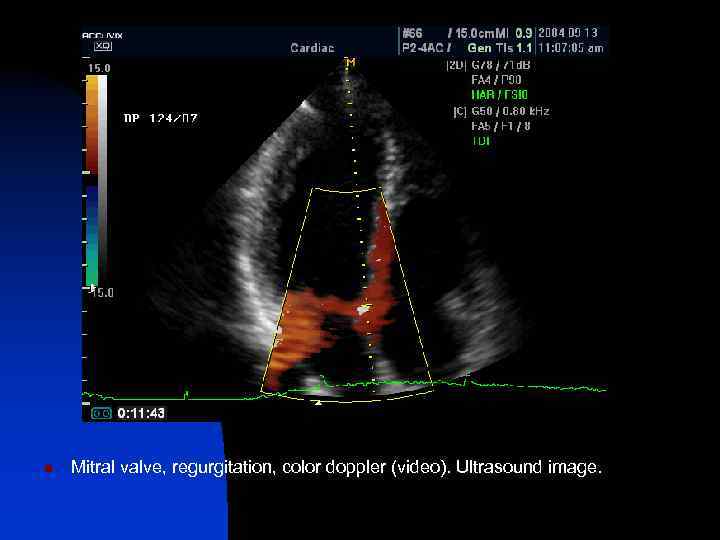

n Mitral valve, regurgitation, color doppler (video). Ultrasound image.